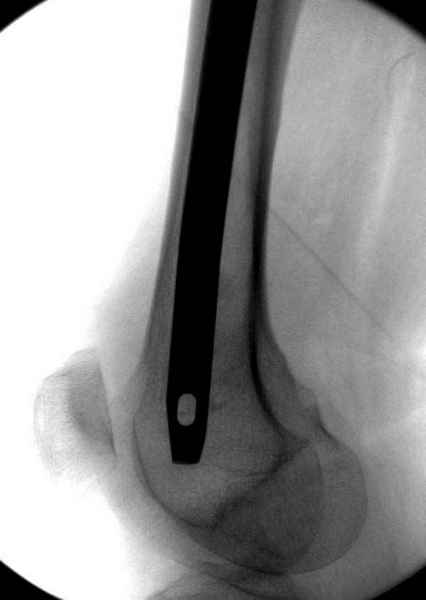

в течение первых 72 часов после перелома, остеосинтез тремя спонгиозными шурупами.

Профилактику дальнейшего раскола неполного перелома шейки провели тремя канюлированными шурупами.

На второй день после выписки упал дома. Снимки приложены. Коллеги рекомендуют удаление шурупа и вытяжение. Что делать?